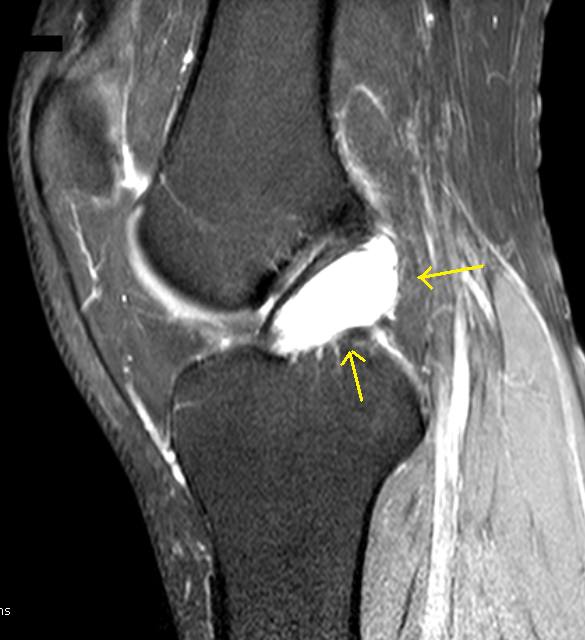

Ganglion Cyst of ACL-MRI

Young male with pain knee joint with lachmann test negative shows a well defined, regular, lobulated, complex fluid signal intensity, space occupying lesion replacing the body and femoral attachment of the ACL with presence of internal septae, with rest of the study unremarkable – Ganglion cyst of the cruciate ligament is likely. Case submitted by Dr MGK Murthy.